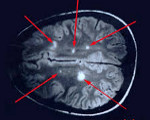

Морфологічно відзначається периваскулярная інфільтрація макрофагами, лімфо і моноцитами, дисеміноване запалення, периваскулярная демиелинизация, дегенерація олигодендроцитов. Уражається переважно біла речовина церебральних і спінальних структур, але можливо залучення і сірого мозкової речовини. Вогнища демієлінізації в ЦНС можуть бути візуалізовані за допомогою МРТ.

Найбільш достовірним методом, що дозволяє діагностувати розсіяний енцефаломієліт, є МРТ головного мозку . У режимах Т2 і FLAIR визначаються погано окреслені асиметричні гіперінтенсивні осередки в білому, а нерідко і в сірій речовині мозку. Вони можуть мати малий (менше 0,5 см), середній (0,5-1,5 см) і великий (більше 2 см) розмір. У деяких випадках реєструються великі зливні вогнища з перифокальним набряком, що викликають мас-ефект - усунення оточуючих структур. Можливе додаткове залучення зорових горбів. У великих запальних ділянках можуть відзначатися крововиливи. Накопичення контрастної речовини в осередках має різну інтенсивність. У 10-30% випадків вогнища виявляються в спинному мозку.

Всім пацієнтам, які перенесли гострий епізод РЕМ, через 6 міс. рекомендовано повторне проходження МРТ. Зникнення або зменшення ділянок демієлінізації за цей період є основним підтвердженням діагнозу «розсіяний енцефаломієліт» і дозволяє виключити розсіяний склероз. При цьому повне зникнення запальних ділянок реєструється в 37-75% випадків, а скорочення їх площі - в 25-53%.